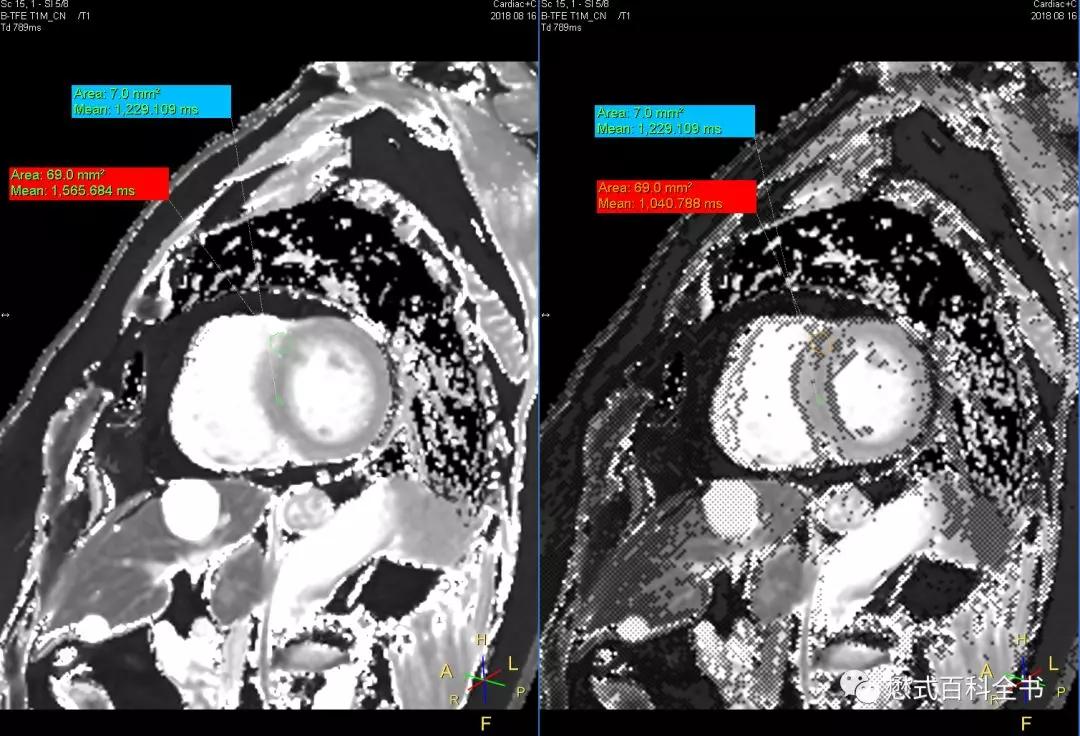

图17:T1 map图,左侧是测出来的T1值,右侧是校正以后的T1值Confidence map

如上图所示,T1 mapping扫描完,可以得到T1 map图。左侧是T1 map,右侧是校正以后的T1值,也叫Confidence map。右侧图像里面的小点代表测出来的T1值可能不准。

如上图所示,这是我在场地,扫描完的一个心脏T1 mapping序列,得到的T1 map。我做了一个实验,在左侧和右侧,各划了两个感兴趣区ROI。蓝色的感兴趣区,在左侧图和右侧图位置一样,在右侧图避开了小点(也就是值不一定准确的点),得到的T1值都是一样的,左右均为1229.109ms;红色的感兴趣区,在左侧和右侧位置也一样,不同的是,在右侧位置,这个感兴趣区包括了太多的小点(也就是值不确定点),得到的T1值是:左侧为1565.684ms;右侧为1040.788ms。两侧是不一样的。

所以,在进行T1值的测量的时候,最好参照右侧的图,划感兴趣区尽量避免把小点包含进去,否则值可能不准。

那么心脏T1 mapping扫描得到的T1 map为什么有这么多unconfident pixels也就是不置信点区呢?

主要原因是motion,也就是运动。我们知道,扫描心脏,会进行心电门控和呼吸运动的冻结。我们做心脏T1 mapping一般是采用屏气序列扫描的,如果被检查者屏气不好,则不能保证在心脏序列扫描的时候,不同TI时间得到的像素是匹配的,这样就会造成不置信值出现。